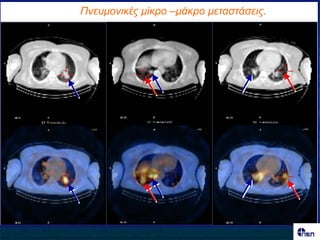

Γοκαίθα 62 εηώκ - Υεηνμονγεζέκ πνμ εηώκ ζειώδεξ Ca ζονεμεηδμύξ - Μεγάιε ημπηθή οπμηνμπή. - Απεηθόκηζε μεηά από ζεναπεοηηθή πμνήγεζε Ι-131 Ant Post

Πλεσκοληθές κίθρο –κάθρο κεηαζηάζεης.